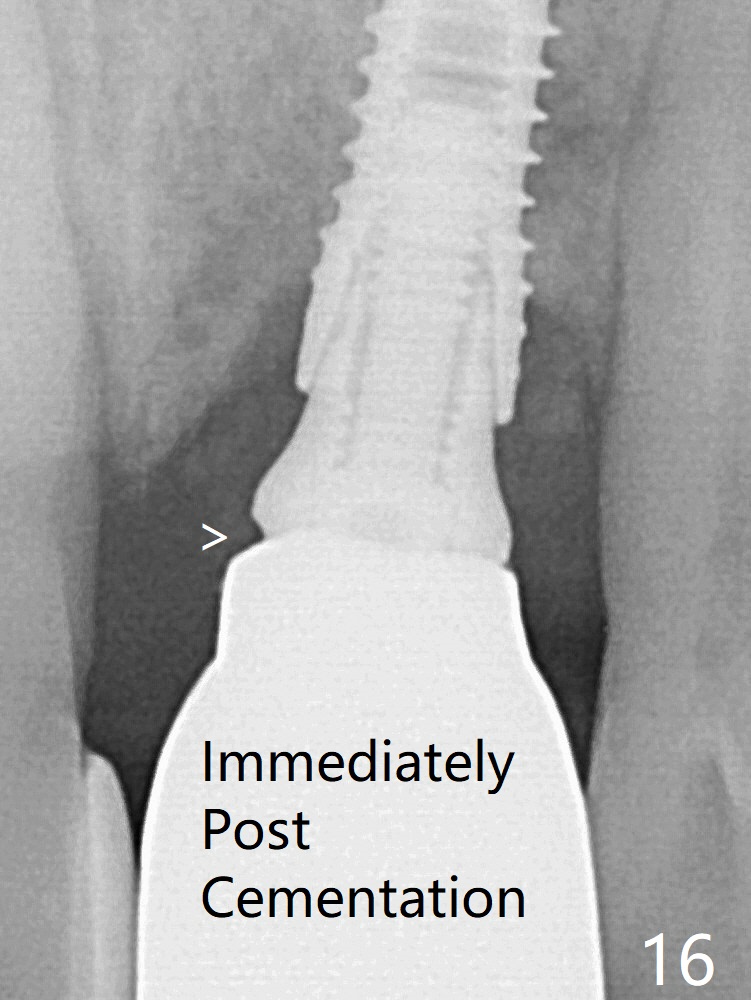

After placement of a 3.8x15 mm implant, PRF is laid against the inner surface of the buccal defect and allograft (Fig.5 *) is packed mainly in the buccal gap before and after insertion of a 4.5x5(4) mm abutment. The bone graft remains in place 3.5 and 4.5 months postop (Fig.11,12 *). Between 3 and 4 months postop, the mesial surface of the abutment has been trimmed (Fig.12 >). Since the mesial surface of the tooth #10 will be reduced (white curved line) to correct the upper dental midline, an angled abutment (red line) seems to be necessary to shift the provisional distal. The socket at UL1 seems to have healed except the most coronal 1 year 3 months postop (Fig.14 *). The final crown has an open margin (Fig.16 > (nearly 1 year 4 months postop)), partially due to less ideal trajectory. Guided surgery could solve the problem. Sticky bone may restore the buccal plate defect.